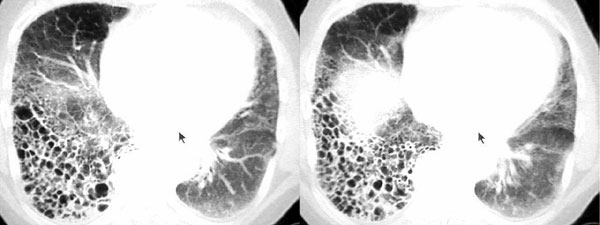

以下是引用dyqct在2006-9-10 13:57:00的发言:[br]右肺下叶呈蜂窝状改变;左且舌段亦见多数条状高密度影,边界不清,下叶见多数磨玻璃样影,并可见胸膜下线。[br]考虑:间质纤维化(后期改变,蜂窝肺)伴感染、支气管扩张。

以下是引用袁张锋在2006-9-10 21:28:00的发言:[br]右肺下叶呈蜂窝状改变;左且舌段亦见多数条状高密度影,边界不清,下叶见多数磨玻璃样影,并可见胸膜下线。[br]考虑:间质纤维化(后期改变,蜂窝肺)伴感染、支气管扩张。